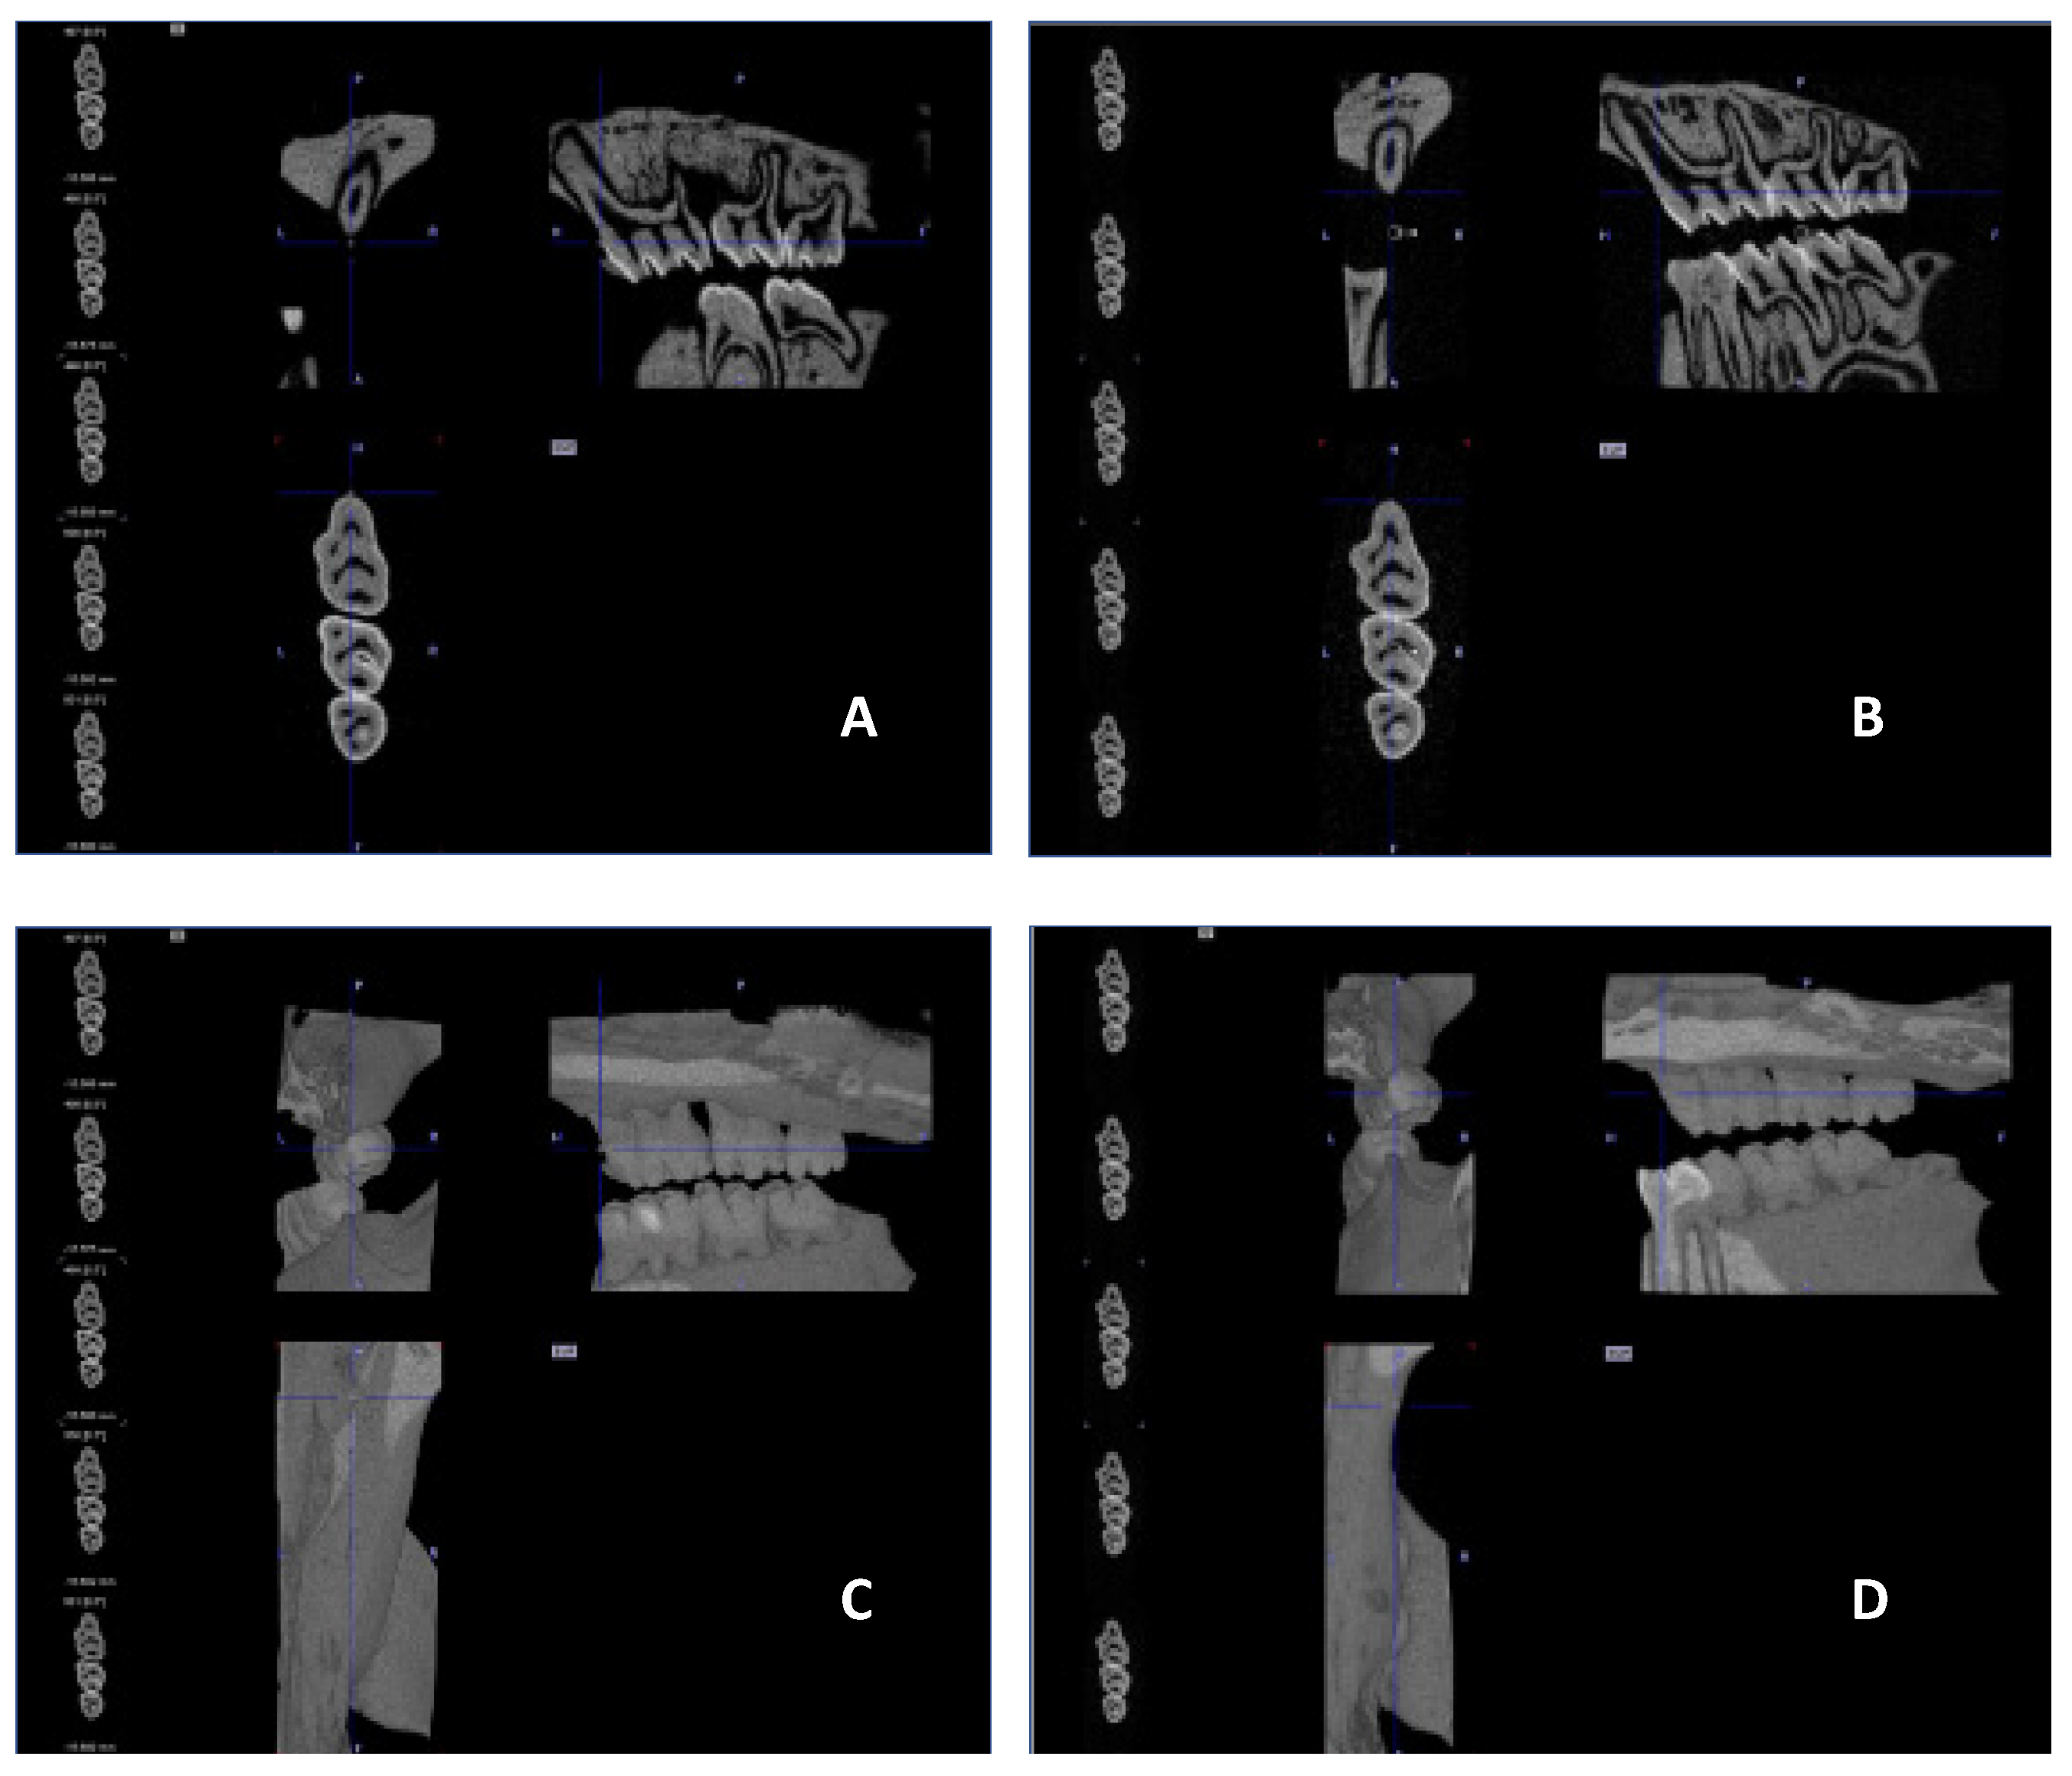

No visible changes were noted in the periodontium. Furthermore, CT scans revealed no alterations in the jawbone area. Due to technical constraints, the experiment was confined to the upper jaw, and alveolar bone loss was quantified using micro-computed tomography (μCT). Measurements were taken from the cemento–enamel junction (CEJ) to the alveolar bone crest (ABC). For each analyzed rat (23 in total), 12 measurements were conducted: three times per molar at two sites (left and right), doubled for statistical replication. The specific distances utilized for statistical analysis are detailed in Figure 8.

Figure 9 presents a representative CT analysis of bone loss in P. gingivalis-infected animals (both minocycline-treated and controls. The beneficial effect of the treatment is clearly visible with regard to bone loss. Comparison of the CEJ-ABC distance shows a significant bone loss in the non-treated animal (A + C, PG), which was remarkably diminished by the treatment (B + D, PG+MIN-T).

This observation has been statistically validated, as shown in Figure 10. Aggregated measurements across all evaluated molars (1st, 2nd, and 3rd upper molars) indicate a significant reduction in bone loss in the treated group PG+MIN-T, with a p-value of <0.0001 compared to the non-treated group (PG). This demonstrates the antibiotic’s effectiveness over 31 days following treatment with the novel formulation.

To determine bone loss High Resolution Animal Computed Tomography (Micro-CT, MILabs, The Netherlands) was used. All animals were scanned at two time points (before treatment (T0) and on the day of termination of the experiment (TEND)). Imaging was performed at an ultra-focus magnification, 50 kV source voltage, and 0.21 mA current. Three-dimensional images were obtained using the PMODE software (vers. 4.3; Fällanden, Switzerland). To assess the alveolar bone loss, a linear distance from CEJ to ABC of each tooth of the lower and upper jaw was measured. Each measurement was performed three times, and the data are presented as the mean ± standard deviation (SD). The results are presented as the distance after subtracting the basal measurement (T0) from the measurement obtained at the endpoint of the procedure (TEND).